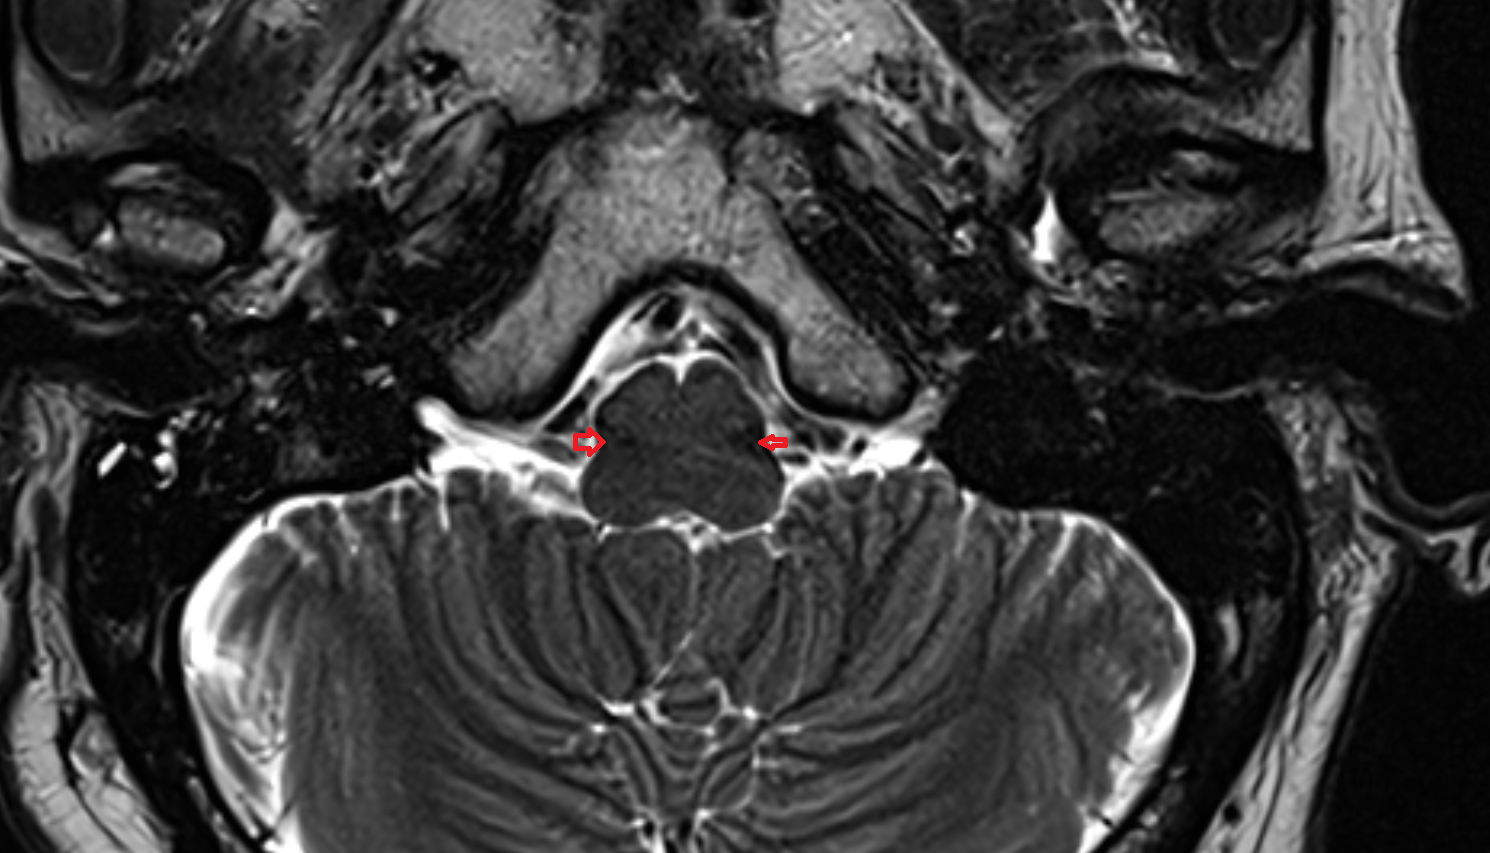

- Lateral aperture of fourth ventricle (foramen of Luschka)